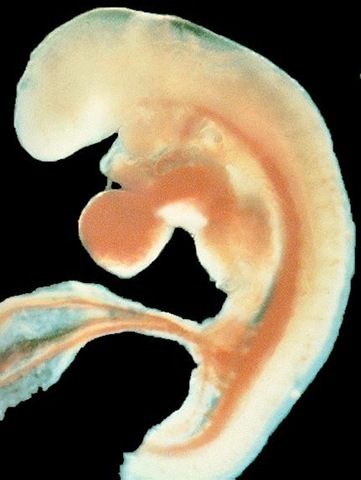

• SEMANA 3

SEMANA 3

El cerebro se divide en 3 secciones principales

Prosenfalo

Mesefalo

Rombencefalo

y su vez desarrolla el aparato respiratorio y digestivo.

aparece el corazón tubular